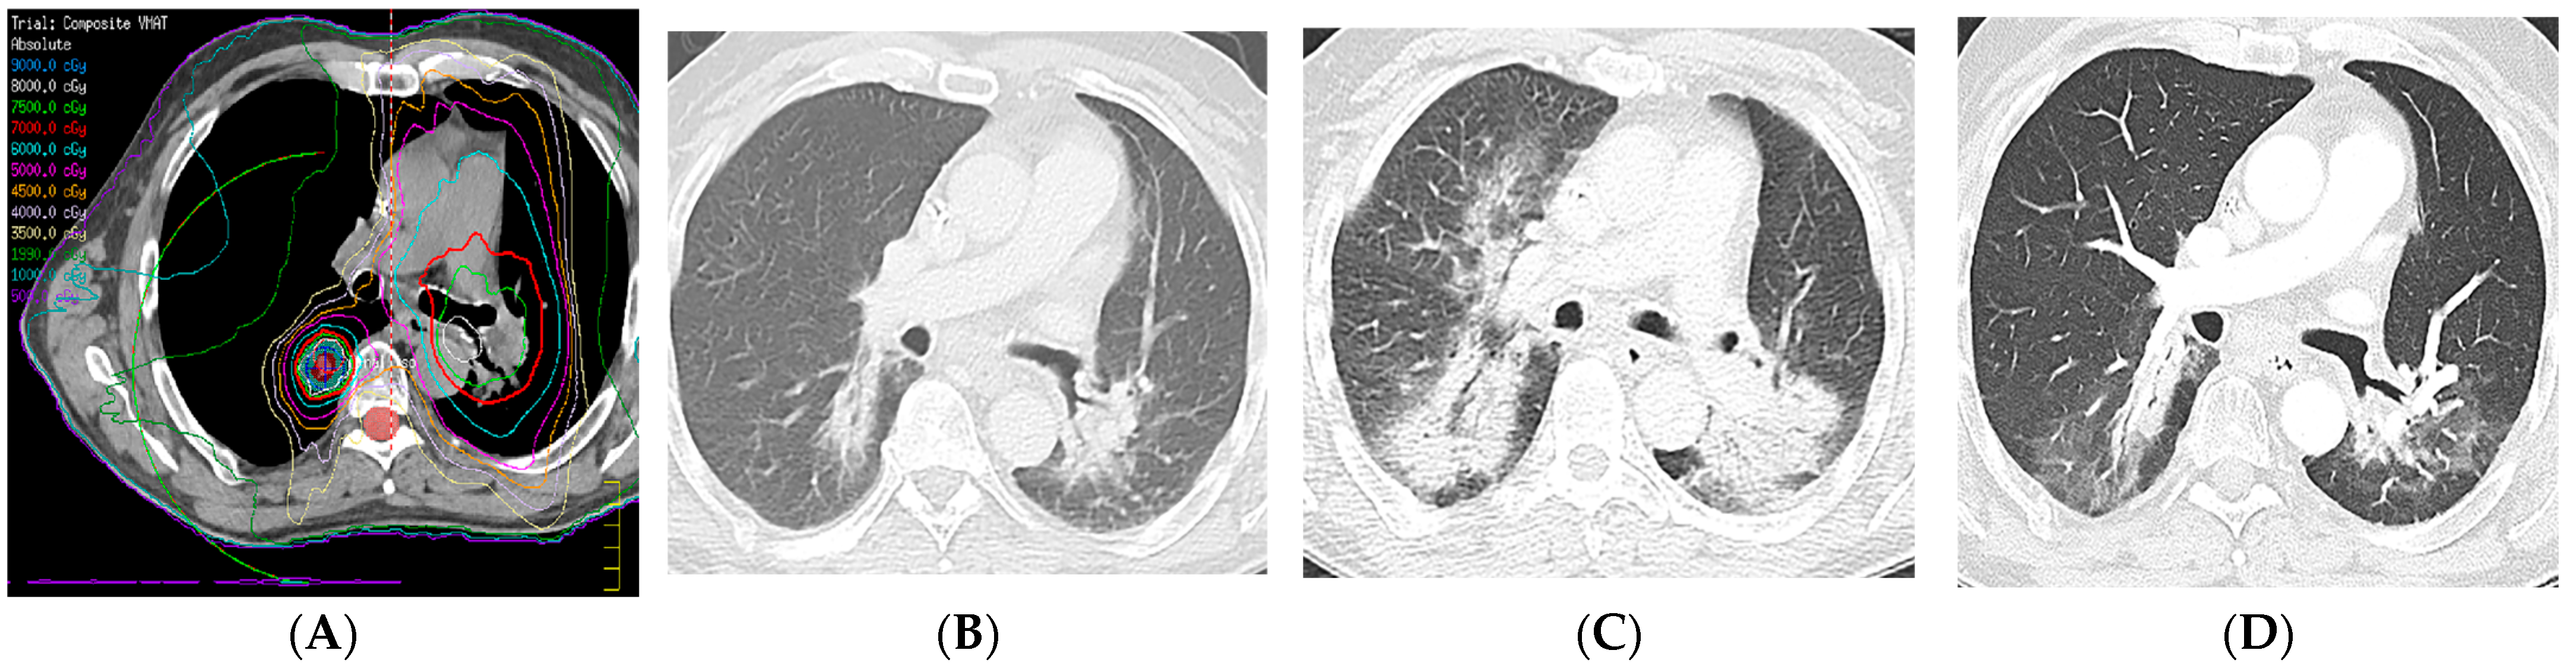

7.2. Radiation Recall Pneumonitis